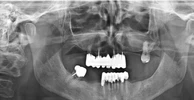

Implant tedavisi